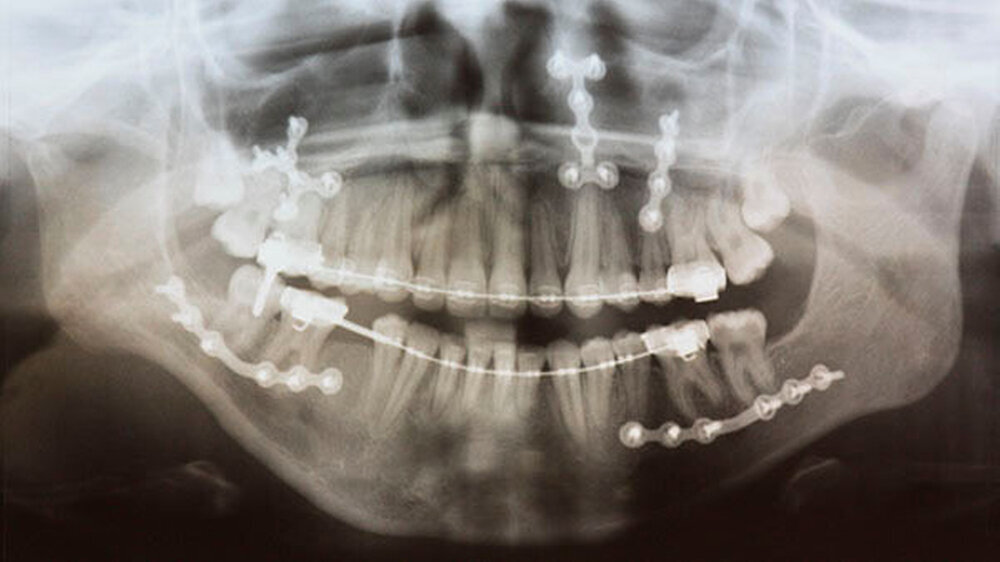

Mit der virtuellen Planung, individuellen Kiefergelenkprothesen und einer zusätzlichen Rückpositionierung des Oberkiefers in die ursprüngliche Lage erfolgte dann die Operation. Alles erfolgte in einem Operationsgang. Die Bonner MKG-Chirurgen fertigten die Endoprothesen für die Frau individuell im CAD-/CAM-Verfahren an. Dafür wurden die Daten der Computertomografie des Schädels zugrunde gelegt.

Durch diese hoch anspruchsvollen Verfahren ließ sich annähernd die ursprüngliche Position des Unterkiefers vor der Einschmelzung wiederherstellen; in der gleichen Operation wurde die Position des Oberkiefers der jetzt idealen Stellung des Unterkiefers angepasst.